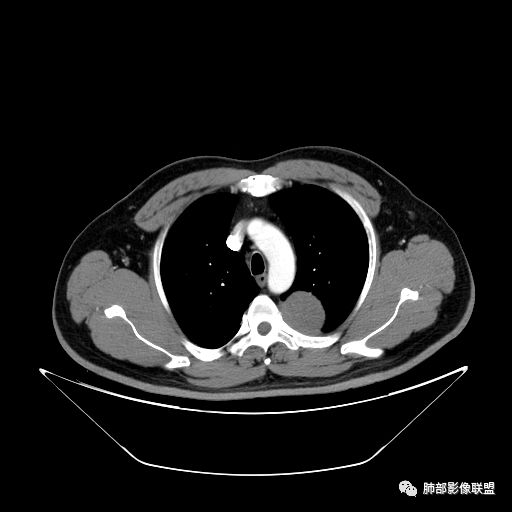

曹志勇:右肺尖后段类圆形病灶,边界清边,缘锐利,宽基底与胸膜相连,环形强化,内似见蛇纹血管征,考虑胸膜孤立性纤维瘤,右肺外底段病灶,考虑炎性可能大

张帅:患者中年男性,咳嗽 咳痰3月,痰为白色粘痰,左上肺病灶,边缘光滑,周围未见毛刺 分叶,肺组织受挤压,与胸膜关系密切,部分层面与胸膜脂肪间隙消失,有胸膜尾征,病灶定位于胸膜,病灶增强可见强化,边缘可见增强血管,内可见低密度区,考虑 孤立胸膜纤维瘤?神经鞘瘤?右肺下叶外基底段病灶,病灶与胸膜有牵拉,病灶边缘光滑,平直 u型征,未见明显毛刺,增强病灶内可见增强血管影,边缘低密度,考虑病灶内存在痰栓。右下肺病灶考虑良性炎症性病灶,ABPA?

可芸:定位:肺外病变,胸椎旁肿块,边缘清晰光整,可见胸膜尾征无支气管进入,肺组织受压。轻度强化,密度稍不均匀,未见肺动脉供血,考虑良性肿瘤,神经源性,孤立性纤维瘤?右肺下叶病灶,轻度强化,血管显影,边缘平直、凹陷,炎性病变。

王秀仙:左侧后纵膈占位,位于胸膜下,胸膜被顶起,有胸膜尾征,密度均匀,轻度强化,内可见斑点钙化。周围肺组织结构推移。右肺下叶可见片状影,沿支气管走行,边缘平直收缩,强化明显,胸膜有牵拉。二元论,考虑1左侧后纵膈神经鞘瘤。鉴别SFT.2右肺下叶炎性肉芽肿。

等待戈多:左侧脊柱旁软组织肿块,边界清楚,肺外胸膜来源,肺组织受压,增强有强化,考虑SFT 鉴别神经源性肿瘤;右肺下叶斑片影,明显强化,边缘平直 考虑炎性病灶。

右叶下叶病变,顺支气管走形成不规则片样,考虑炎性

Shelia??:左下胸腔脊柱旁类圆形软组织肿块影,呈D字证,可见胸膜掀起,邻近肺组织受压呈弧形致密影改变,增强后似轻度均匀强化,邻近骨质未见明显异常,考虑良性病变,孤立性纤维瘤?鉴别神经源性肿瘤另外右肺小叶不规则病灶,边缘平直收缩为主,局部可见弓形凹陷,密度均匀,增强后轻中度均匀强化,周围肺野尚清晰,考虑炎性肉芽肿病变,OP?但是感觉周围太光整,还是就是慢性炎症?

田园晚风:左胸后部近胸椎占位,密度均匀,边缘光滑,呈d字征,外侧可见压缩肺组织,右肺见条状致密影,与支气管走行一致,考虑左侧神经源性肿瘤,右肺abpa?

张小兵:老年男性,慢性病程,咳嗽咳痰3月,左下肺脊椎旁沟区见宽基底类圆形软组织肿块,无分叶,瘤肺境界光整,其内见点状钙化,周边肺组织挤压,胸膜尾征,延迟强化,提示内含纤维成分,考虑神经源性肿瘤,SFT可能。右下肺病灶收缩力强,内见扩张支气管,提示慢性炎症,考虑机化。

另外右肺病变,平直收缩,应该与左边病变二元,目前感觉炎症,强化均匀